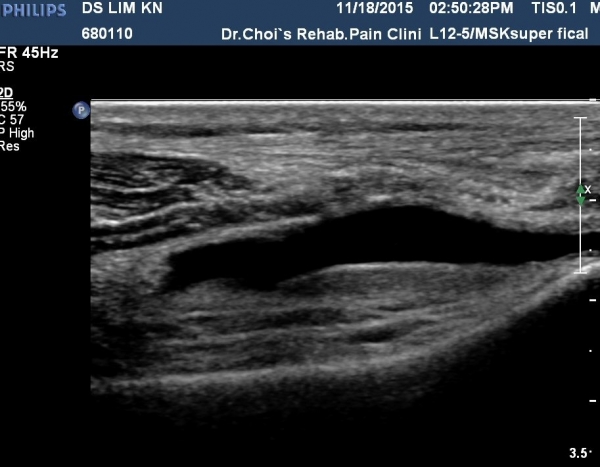

¹«¸­À§  ³»Ãø sartorius Ⱦ´Ü¸é°Ë»ç¿¡¼­ sartorius¿Í ³»Ãø ±¤±Ù »çÀÌ¿¡¼­ saphenous ½Å°æÀÇ ½½°üÀý ºÐÁö°¡ °üÂûµÊ(»çÁø 3).